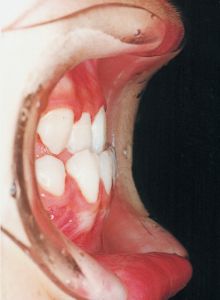

Although there were many missing deciduous teeth, the number of permanent teeth was not problematic (4). The amount of negative overjet was significant (1). On cephalometric radiographs, the mandibular ramus was not relatively long, but the large gonial angle and the long mandibular body were noticeable, indicating an overall tendency of the mandible to project inferiorly and anteriorly. High lower facial height was also characteristic.

A potential predisposition to mandibular protrusion was clearly evident.

Aware that treatment would be challenging, we proceeded with the first phase of treatment based on the current functional status and anticipated developmental implications (7). During the mixed dentition phase, the body responds readily to treatment, allowing for relatively rapid tooth movement and changes in jaw position (8,9). Subsequently, once freed from mechanical stimulation, growth continues according to inherent predispositions, often appearing to disregard occlusal functional efficiency (10,11). These changes are clearly observable on cephalometric radiographs (12). After confirming the extent and direction of growth, we decided to incorporate surgical intervention into the treatment plan and wait until the age when growth begin to decline.